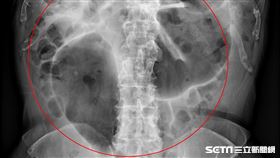

他腸扭成咖啡豆狀!痛到屁放不出險亡

一名80歲趙伯伯連續多天腹脹,連排便和放屁都變得困難...

2019/12/31 10:20